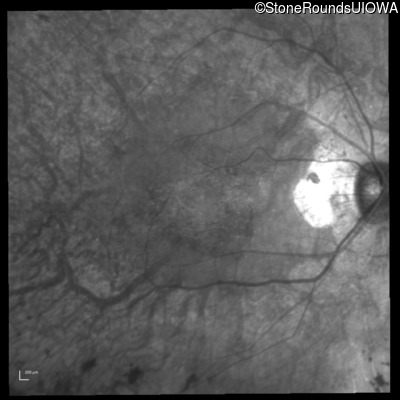

Infrared Fundus Photograph - Right - 20/25 -3

Exemplar